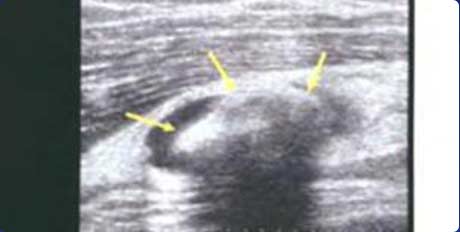

超声图像中出现的以高回声为主的高低回声混杂的团块即为痛风石,一般表现为高回声、不均质、界限不清楚、边缘可见液性暗区,可伴有声影。超声通过对痛风患者皮下组织、软骨、滑囊、韧带等不同部位痛风石的不同表现形式(滑膜结节厚度、强回声团状数量、回声是否伴声影)的清晰观察,能对痛风石进行区分(软性痛风石或硬性痛风石),帮助制定患者的个体化、针对性治疗方案。

超声发现不同形态痛风石,对痛风石定性